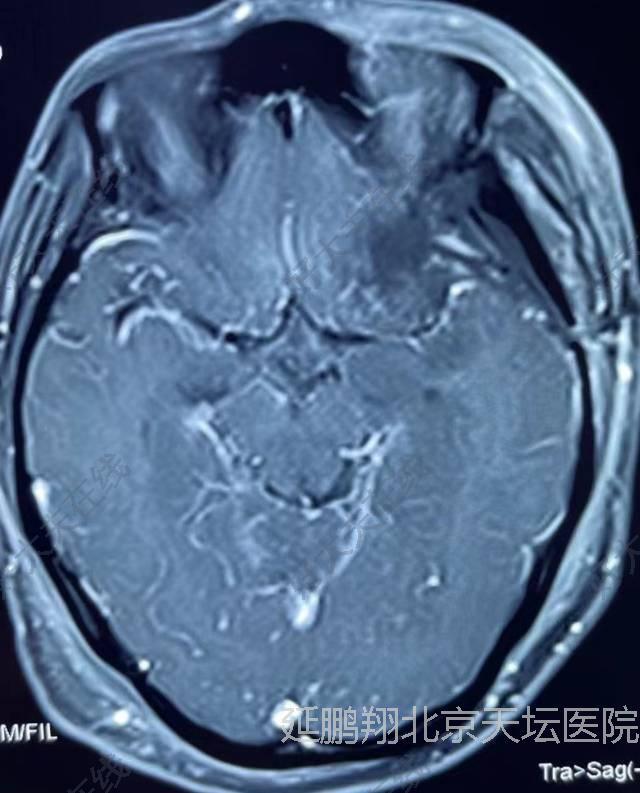

- 治疗后7天

患者恢复顺利。复查核磁肿瘤消失。